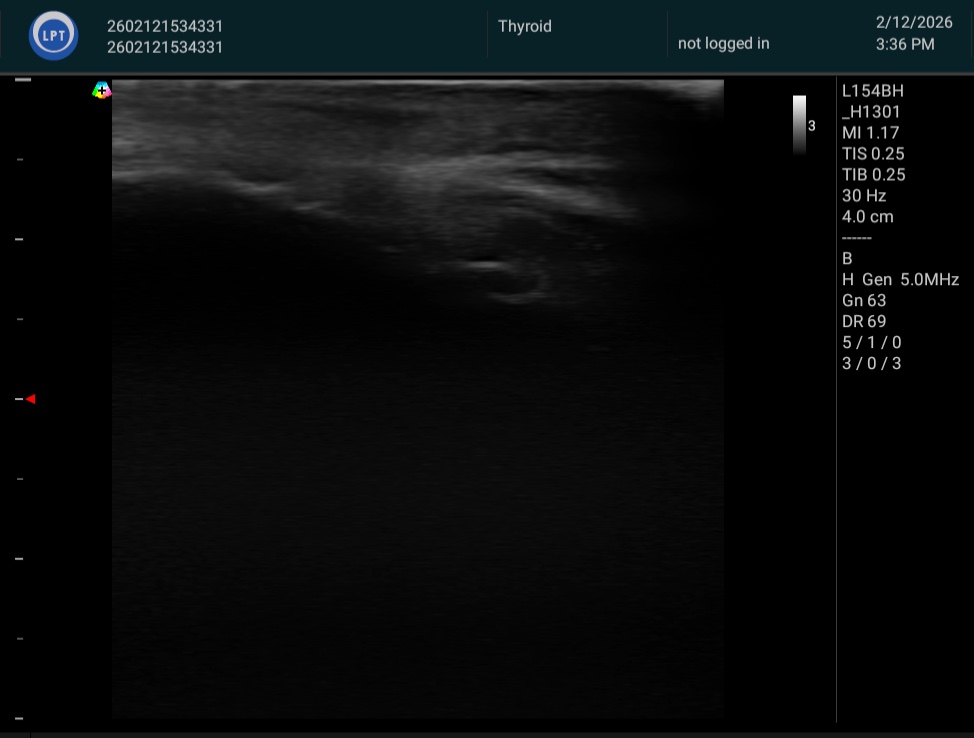

施術前後の変化をエコー画像・ノギス計測によって客観的に記録しています。

脂肪体が「膨らむ」——その事実を、数字と画像がそのまま示しています。

すべて、たった1回の施術後の計測です。

※ 個人差があります。掲載の計測値はすべて実際の施術前後の計測結果です。

※ エコー画像・ノギス計測は施術効果の参考として提示しています。